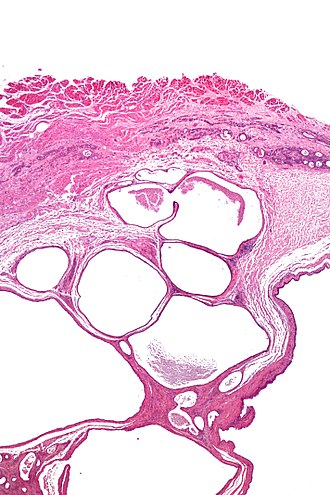

Cystic tumour of the atrioventricular nodal region. H&E stain. | |

| LM | cystic spaces lined by single layer of bland epithelial cells, +/-focal mononuclear inflammation, +/-psammoma bodies |

Microscopic

Features:[4]

- Cystic spaces lined with single layer of epithelial cells.

- +/-Focal mononuclear inflammation.

- +/-Psammoma bodies.